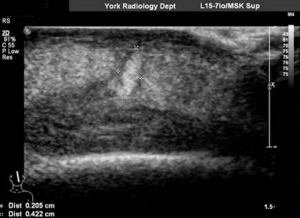

واكتشف الأطباء في النهاية أن هناك تجويفًا تحت النتوء، ووفقاً للطبيبة فرح شاهي، أخصائية الأمراض المعدية في مستشفى يورك التعليمي، ربما كان داخل التجويف ذبابة صغيرة أو يرقة.

وعالج الأطباء النتوء بالهلام، لمنع تدفق الهواء، ودفع الحشرة إلى سطح الجلد، وفي نهاية المطاف، تمت إزالة اليرقة الحية، وإحضارها إلى مدرسة لندن للطب الاستوائي.